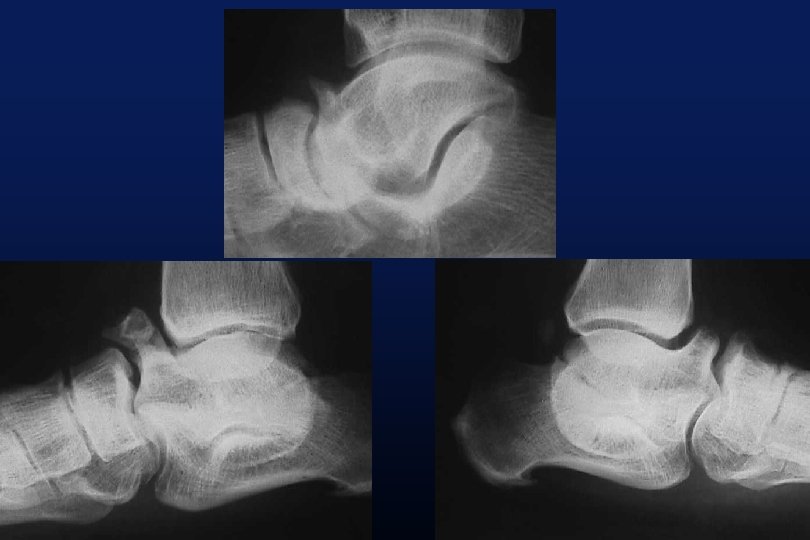

LES SYNOSTOSES DE L ’ARRIERE PIED Coalitions Tarsiennes (Tarsal Coalitions)

CALCANEO NAVICULAIRES (60%) TALO CALCANEENNES Synostoses et coalitions tarsiennes chez l'enfant. Étude de 68 cas chez 47 patients Ph. Rouvreau, J. C. Pouliquen, J. Langlais, C. Glorion, G. de Cerqueira Daltro The Too-Long Anterior Process Calcaneus: A Report of 39 Cases in 25 Children and Adolescents Pouliquen, J. C. M. D. ; Duranthon, L. D. M. D. ; Glorion, Ch. M. D. ; Kassis, B. Journal of Pediatric Orthopaedics Volume 18(3) June 1998 333 -336

Comfort 1998 Résection Coalition / surface sous talienne > 1/3 75% de mauvais résultats < 1/3 77% de bons résultats.

TRAITEMENT ADAPTE A LA PLAINTE ANTALGIQUE

ORTHESES PLANTAIRES RESECTION ARTHRODESE